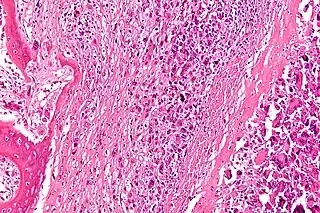

![]() Micrografía de un osteosarcoma, un cáncer óseo primario. | ||

- Osteosarcoma: es la variante más común. Se desarrolla en el tejido nuevo de los huesos en crecimiento (osteoide).